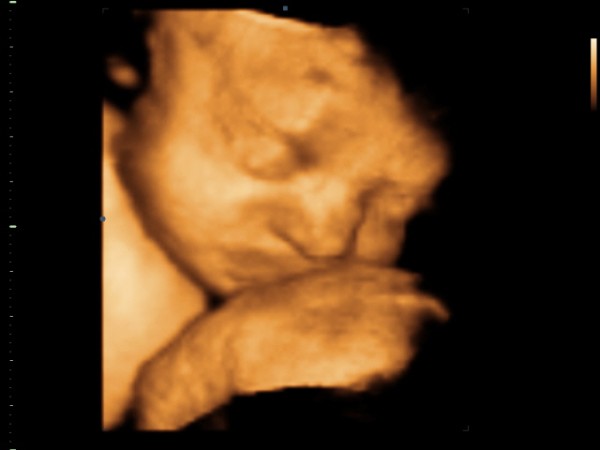

Az első adagban voltam ma, egy teremben volt 6 készülék és ágy, lelkes népes nézőközönség, sok magyarázat. Átlagban egy órát nézték a babókat, nekem sikerült 2 órát lennem ott!!!!!!!!!!!! Iszonyat, milyen alaposak voltak! Mivel bemutató előadás volt, így olyanokat is néztek, amiket máskor nem, vagy csak nagyon indokolt esetben. Kezdték az életjelenséggel, a szívvel. Minden üregét, aortát, több nézetből, szeletekből, mélyebbről, szóval sokat nézték. Minden oké. Volt gerinc, bordák, agy, flow- és szívhang-hallgatás, szemek és szájpadlás-vizsgálat is, mindent magyarázott a dokiknak a dokibá, de rám is figyelt, ha kellett és fontos volt, nekem is "fordított". Jobb oldalamon a dokik, balomon a kivetítő, így mindent kényelmesen láttam. Emő eleinte tiltakozott, s bár az egyik keze végig az egyik szeme előtt volt, a végére sikerült jó fotót csinálni róla. És képzeljétek, megkaptam azt a 8 fotót, amit csináltak CD-n, pedig arról volt szó, hogy nem lesz felvétel! Így nektek is meg tudom mutatni Emőkét! Voltak mérések is, tökéletesen egyezik a kora és a mérete (24 hét 1 napos, méretek 24 hetesek), becsült súlya 580gramm, várható születési súlya 3 kiló. És továbbra is kislány. Very Happy A doki olyan rendes volt, kicsit ki volt akadva, hogy miért nem hoztak nekünk kispárnát, úgy kényelmesebben feküdhettünk volna. Amikor a szívvel "dolgoztak" (egy merevített képpel), oldalra fordulhattam, mert biza a keresztcsontom azért elfáradt a hosszú fekvésben. Jól esett a pihenő, s közben Emő is hajlandó volt picit elfordulni, így lehetett szép képet is csinálni. Iszonyat nagyokat rúgott közben, csak úgy ugrált a hasam.

Lényeg a lényeg: minden a lehető legtökéletesebb rendben a kisasszonnyal!!!!!!!!!! (Bárcsak Borival lett volna hasonló lehetőségünk... :cry: )

Kép

Ugye, milyen szép? Nagyon hasonlít ő is az apukájára!!!!!!!!!!!! Ugyanaz a gyönyörű pisze orrhajlata van, mint a nővérének, imádom!!!!!!!!!!!